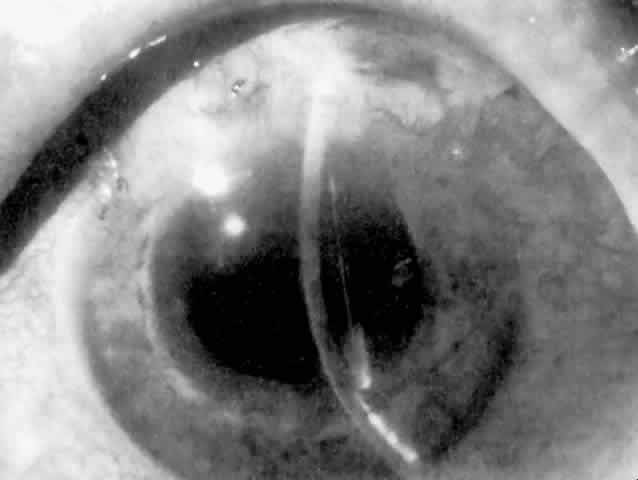

IOL-related inflammation is more commonly associated with some styles of lens implants than with others. Position of the lens or foreign material deposited on the lens during manufacture can also account for persistent inflammation. When the inflammation is associated with hyphema, it is termed UGH syndrome, which involves the triad of uveitis, glaucoma, and hyphema. UGH syndrome occurred more frequently in the 1970s, when iris-fixed lenses were commonly used.66,67 Today it is more often associated with anterior chamber lenses and is less likely to occur with posterior chamber lenses, although this has been reported.68,69 The mechanism is believed to be contact of the surface of the lens with the iris, causing mechanical irritation that may be enhanced by a poorly positioned or mobile lens implant. The loose posterior chamber lens may initially exhibit release of pigment due to friction on the posterior surface of the iris (pseudopigmentary glaucoma). This “windshield-wiper” effect alone can produce enough pigment to provoke an increase in IOP; however, it is the erosion into vascular tissue that results in hemorrhage, hyphema, and inflammation (Figs. 4 and 5).

As mentioned in the Persistent Inflammation section, pseudopigmentary glaucoma is in many ways similar to the persistent inflammation that results from an IOL implant. The mechanism is believed to be contact of the surface of the lens with the iris. In persistent inflammation and UGH syndrome, typically either an anterior chamber lens or an iris-fixed lens is the culprit. With respect to pseudopigmentary glaucoma, however, the lens used is more likely to be a posterior chamber lens with the haptics (either one or both) positioned in the sulcus. In this way, the pigmented surface of the iris moves back and forth across the edge of the IOL, promoting release of pigment into the anterior chamber (see Figs. 4 and 5). The mechanism of IOP elevation is outflow obstruction from the excessive amounts of pigment granules and cell debris in the trabecular meshwork.